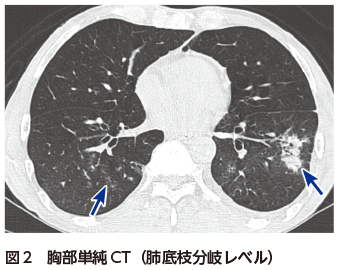

• A1:胸部単純X線写真で両下肺野に浸潤影を認める(図1).

胸部単純X線写真では両下肺野に浸潤影を認める(図1).胸部CTでは両肺下葉の末梢気管支周囲に浸潤影およびすりガラス影の散在を認める(図2).肺底部は胸膜側優位に気管支透亮像を伴う広範な浸潤影を認める(図3).一部は非区域性に分布している(図3).